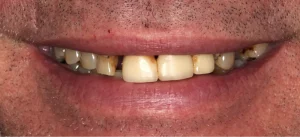

This lady was embarrassed by her yellow teeth and the gaps. The remaining upper teeth were loose from smoking-related gum disease. The upper front teeth were removed, and a temporary denture was placed to allow healing so that the implants could go into a clean bone environment with higher chances of treatment success. A few months later, six upper implants with bone grafting were placed and then a strong porcelain bridge with 12 teeth was fitted on top of the implants.